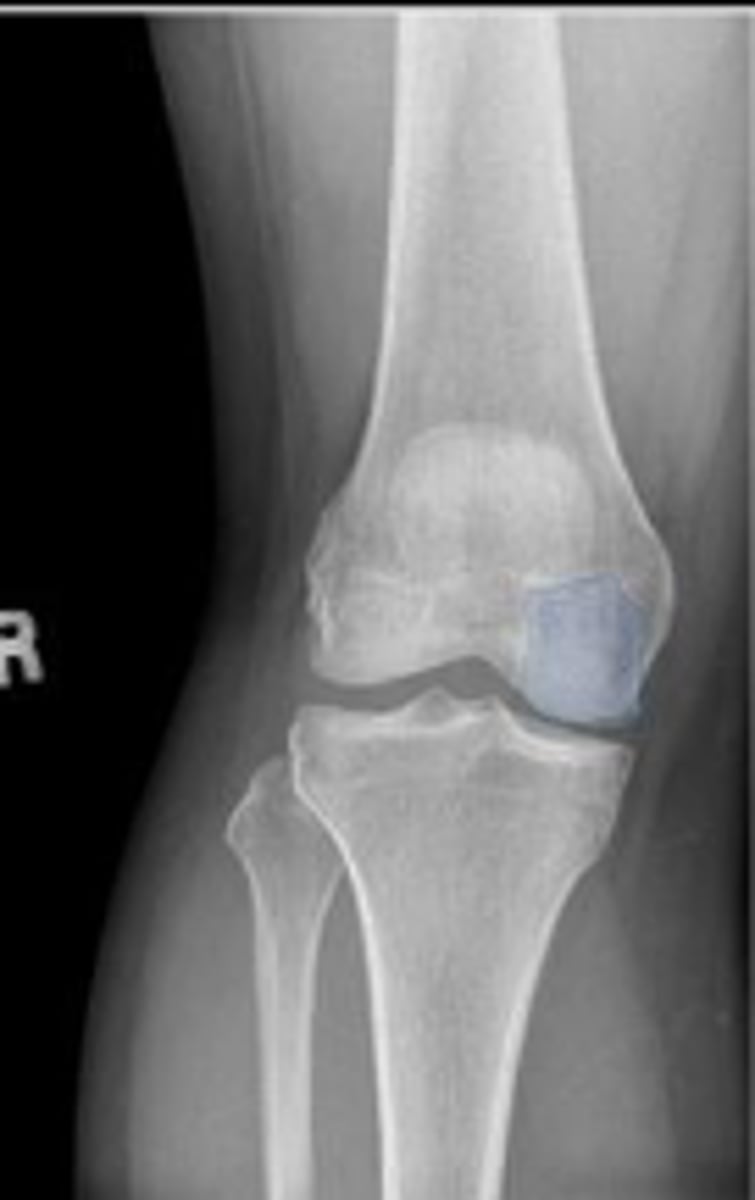

Right AP knee

What is the name of the radiographic view?

Right patella

What is outlined?

Medial condyle of the right femur

Intercondylar fossa/notch of the right femur

Right lateral femorotibial joint space

What joint space is the arrowing pointing to?

Right patellofemoral joint space